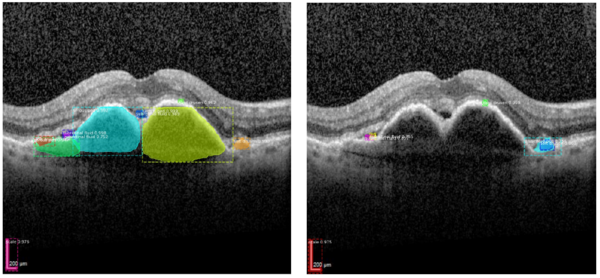

Wir konnten im Rahmen unserer Kooperation mit Prof. Malcherek vom Fachbereich Informatik der Hochschule Darmstadt Deep-Learning-Algorithmen entwickeln, die präzise zwischen aktiver und inaktiver neovaskulärer AMD unterscheiden können. In einem weiteren Projekt wurde ein Deep-Learning-Algorithmus auf das automatische Erkennen verschiedener AMD-typischer Veränderungen auf den OCT-Bildern trainiert. Ein weiterer Schwerpunkt bildet die automatische Erkennung von glaukomatös veränderten Sehnerven bei Glaukompatient:innen. Ein entsprechend mittels Fundusfotografien geschulter Algorithmus erreichte eine gute Trennschärfe zwischen Sehnerven mit glaukomatösem Schaden und solchen, bei denen zwar auffällige Veränderungen, aber kein Nervenfaserschichtverlust bestand. Hier erreichte der Algorithmus bei Hinzuziehen von weiteren Metadaten ein ähnlich gutes Ergebnis wie ein Glaukomspezialist. Weitere Projekte zur Etablierung von Methoden zur Bildannotation sind in Vorbereitung.